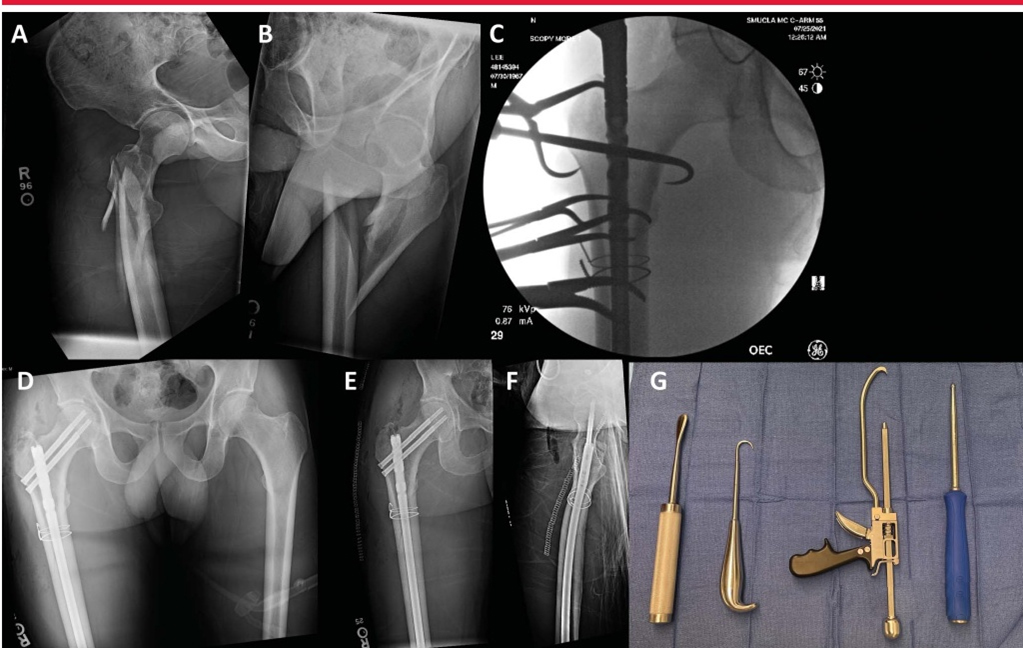

Для репозиции переломов доступны различные вспомогательные методы и инструменты, в том числе заостренные редукционные щипцы, серкляжные проволоки, костные крючки, толкатели шариковых штифтов, коллинеарные щипцы и уникортикальные пластины (изображение ниже).

A и B: травма передне-заднего отдела и боковые рентгенограммы правого бедра, показывающие оскольчатый перелом вертела бедра. C: рентгеноскопическое изображение, показывающее многоточечные редукционные зажимы и серкляжные проволоки, используемые для репозиции. D, AP таз демонстрирует хорошую репозицию околовертельного перелома после операции. E, AP послеоперационное изображение показывает хорошее уменьшение перелома и размещение реконструктивных гвоздей. F: На боковом снимке хорошо позиционированный и хорошо репонированный перивертельный перелом бедра. G: показаны вспомогательные инструменты для чрескожной редукции, включая (справа налево) Кобба, костный крючок, коллинеарные щипцы и шариковый толкатель.